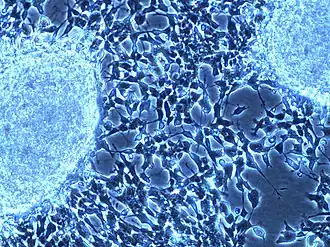

On microscopy, the tumor cells are typically described as small, round and blue, and rosette patterns (Homer Wright pseudorosettes) may be seen. Homer Wright pseudorosettes are tumor cells around the neuropil, not to be confused with a true rosettes, which are tumor cells around an empty lumen.[29] They are also distinct from the pseudorosettes of an ependymoma which consist of tumor cells with glial fibrillary acidic protein (GFAP)–positive processes tapering off toward a blood vessel (thus a combination of the two).[30] A variety of immunohistochemical stains are used by pathologists to distinguish neuroblastomas from histological mimics, such as rhabdomyosarcoma, Ewing's sarcoma, lymphoma and Wilms' tumor.[31]

Neuroblastoma is one of the peripheral neuroblastic tumors (pNTs) that have similar origins and show a wide pattern of differentiation ranging from benign ganglioneuroma to stroma-rich ganglioneuroblastoma with neuroblastic cells intermixed or in nodules, to highly malignant neuroblastoma. This distinction in the pre-treatment tumor pathology is an important prognostic factor, along with age and mitosis-karyorrhexis index (MKI). This pathology classification system (the Shimada system) describes "favorable" and "unfavorable" tumors by the International Neuroblastoma Pathology Committee (INPC) which was established in 1999 and revised in 2003.[32]